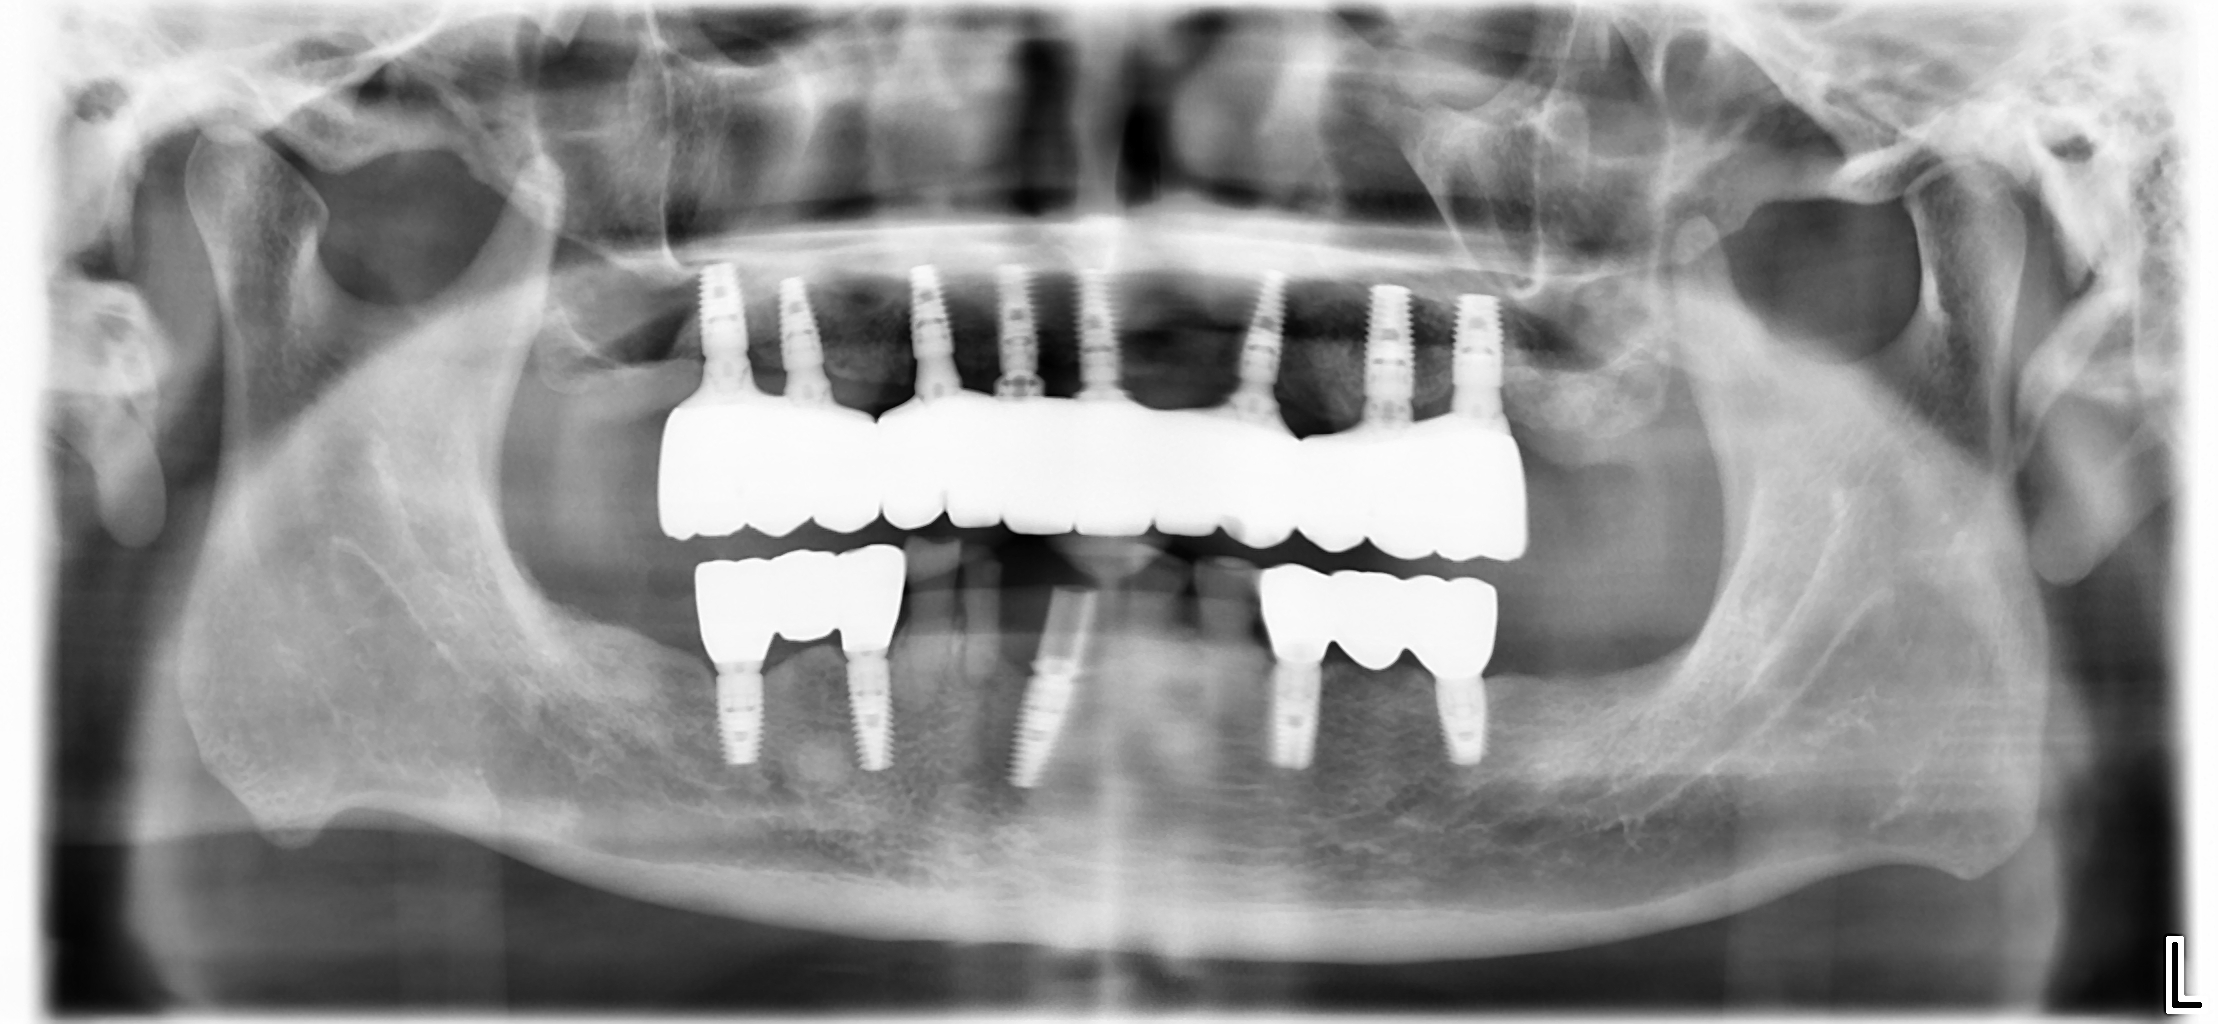

當初石先生來到百世專業牙醫評估時,我透過 3D 電腦斷層掃描 (CBCT) 進行檢查,發現他上顎後牙區的骨頭萎縮相當嚴重。在患者只考慮固定假牙的狀況下,我們有兩個治療選項:

面對石先生後牙區骨頭高度嚴重不足的情況,如果選擇一次ALL on 4 ®的治療,必須以支架將所有的植體連在一起,假牙的清潔比較花費心力。在後牙區無牙的狀況下,單靠四支植體要支撐咬合力超過40年的使用時間,不確定性高。

為了確保整體的長期穩定性,我與醫療團隊決定為他規劃「分階段」的治療方案。

在石先生的第一步治療中,我們先在骨頭條件較好的前牙區進行重建。為了實現當日恢復功能的目標,我運用了以下數位設備:

- 藍光動態導航系統 (X-Guide):植牙導航讓我能在手術中避開神經血管,確保前牙植體定位精確。